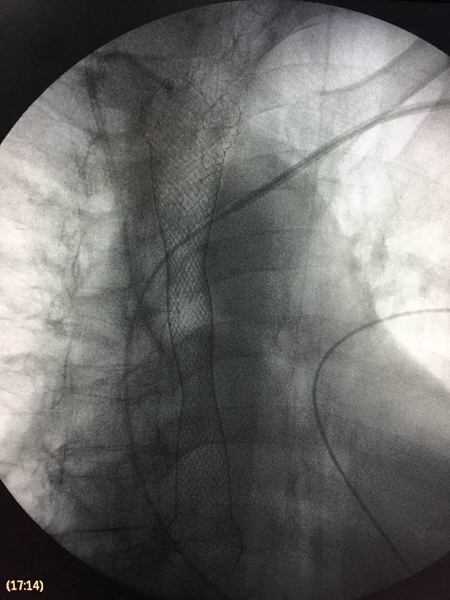

3月20日,消化内科与心内科两科强强联手,当心内科主任阮宏标为老人装完起搏器后,姚必瑜医生接着上阵。“我们通过消化内镜,在病人的食道内放置一长约12厘米的食管支架,支架外层带有一层膜,既能扩张食道,又能封堵瘘口。”姚必瑜说。

手术过程十分顺利,支架一次性置入。术后当天,老人便能喝水,第3天开始进食稀饭,术前呛咳、吞咽困难等症状未再出现。

【CT下食管覆膜支架】